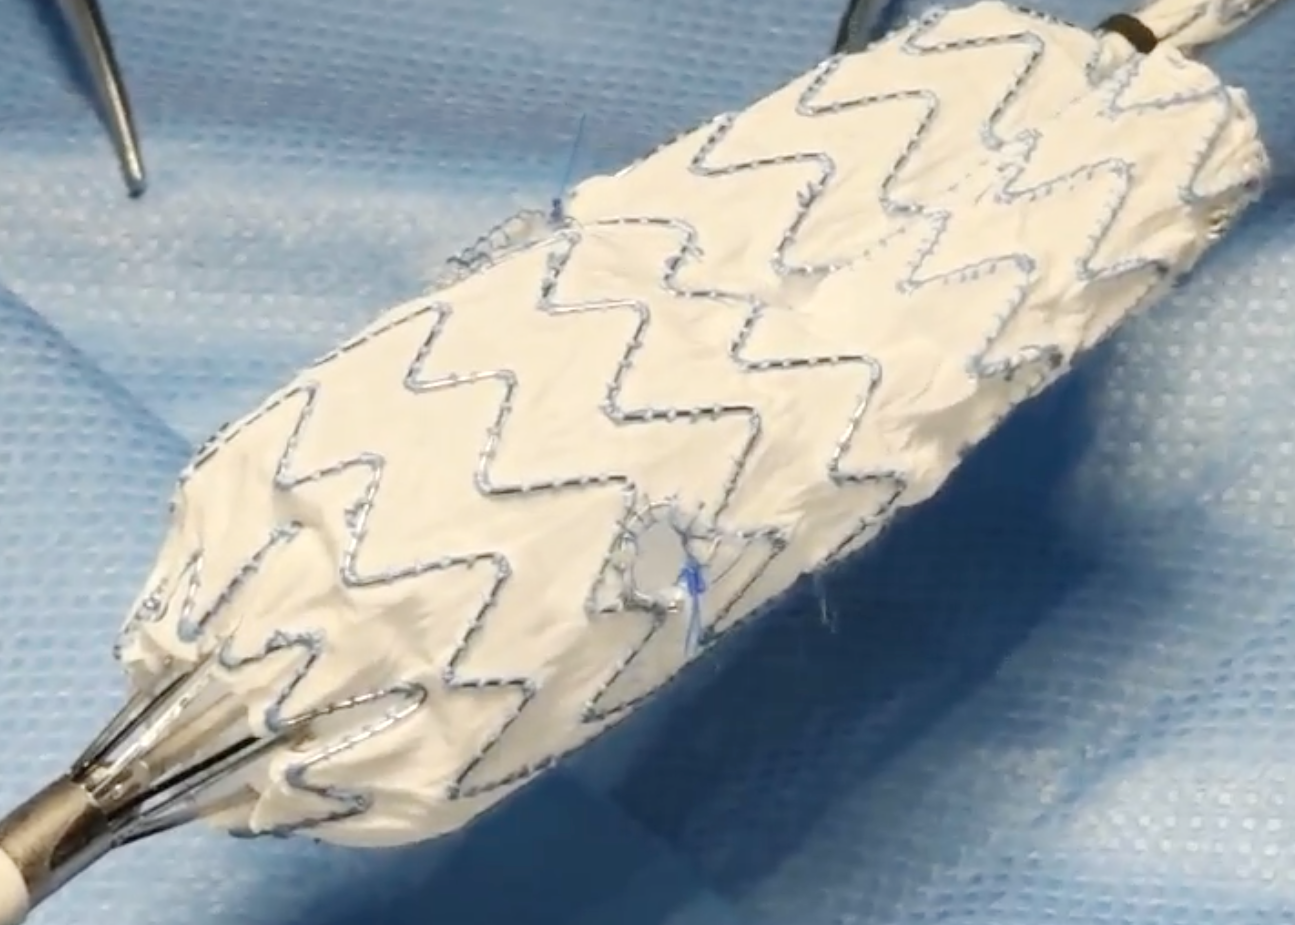

面对挑战,消化内科团队迅速启动多学科会诊。由血管外科驻桂专家王伦常博士、姚松良副主任医师及陈国兴硕士组成的攻坚小组,经全面评估后,决定优先通过微创手术处理动脉瘤。为了不影响后续的结肠手术,团队创新性地采用了PMEG技术,在局部麻醉下为患者施行了左侧髂内动脉瘤隔绝并重建术。术中,团队对支架进行了精准的台上改造与开窗,不仅成功隔绝了瘤体,更完美重建了左侧髂内动脉,保住了至关重要的血液供应。术后,患者恢复顺利,及时转入普外二病区(胃肠外科)完成了结肠肿瘤的治疗,现已康复出院。

术中团队对支架进行精准的台上改造与开窗

心脏问题解决后,治疗的“接力棒”交到了血管外科团队手中。团队预先在腹主动脉支架上为副肾动脉开窗并标记,随后在术中精准定位,将导丝导管通过开窗口超选入副肾动脉并成功植入支架,最终造影显示,腹主动脉瘤被完全隔绝,副肾动脉血流通畅,且无内漏。术后,患者肾功能维持良好,平安出院。

精准“束径”,为支架锚定与隔绝瘤体打下坚实基础

精细“开窗”,为副肾动脉预留生命的“侧门”

值得一提的是,这两例手术的核心——PMEG(医师改良腔内移植物)技术,被誉为血管外科的“定制裁缝”。它要求医生在手术台上,根据患者独特的血管解剖结构,对标准支架进行现场裁剪与开窗,实现“量体裁衣”式的精准治疗。作为处理累及内脏分支动脉的主动脉病变的先进微创方法,该技术主要在国家级和省级血管外科中心开展,桂林医院血管外科是广西为数不多可开展此类手术的科室。